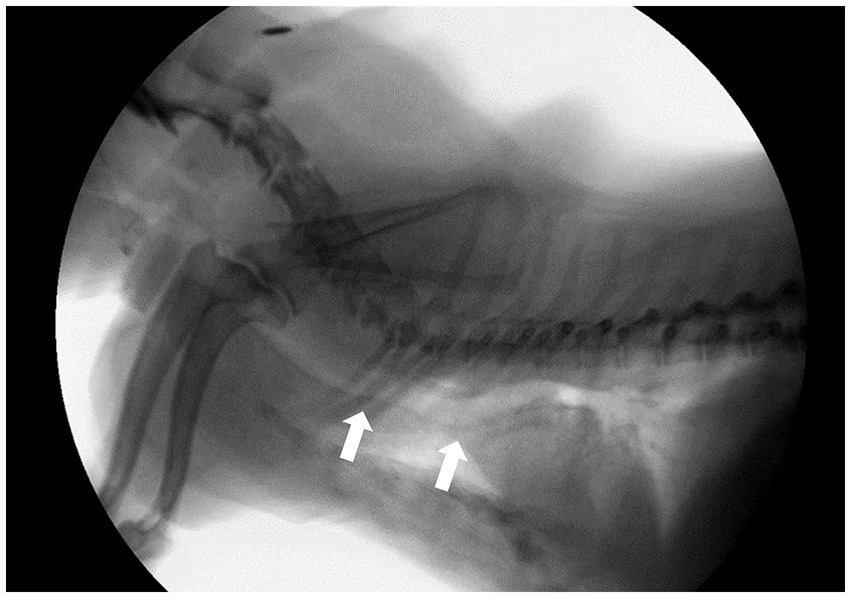

Todos los perros del estudio fueron evaluados para detectar signos clínicos y se sometieron a fluoroscopia para diagnosticar CT (8). También se realizaron estudios radiográficos. Los signos clínicos evaluados incluyeron tos crónica, intolerancia al ejercicio, cianosis, dificultad respiratoria y síncope. Un sistema de radiografía digital disponible en el mercado (EVA-HF 525; ECORAY, Seúl, República de Corea) se utilizó para obtener radiografías torácicas laterales y dorsoventrales derechas durante la inspiración. Partiendo de la hipótesis de que el diagnóstico fluoroscópico era preciso, analizamos si la TC podía diagnosticarse a partir de las radiografías inspiratorias. Fluoroscopia (SPINEL 3G; GEMSS Healthcare Corporation, Paju, República de Corea) se llevó a cabo durante las fases de respiración normal y tos (espiración forzada), con los perros colocados en decúbito lateral derecho. El colapso se definió como una reducción en el diámetro de la luz del ≥25% en la fluoroscopia. Los grados de TC se evaluaron según el grado de colapso máximo del diámetro luminal traqueal (0, 25, 50, 75 y 100%) con base en los criterios desarrollados por Tangner y Hobson (2, 20). El grado de hernia del lóbulo pulmonar cervical (CLLH) se evaluó colocando al paciente en una vista humanoide y comparando el nivel apical herniado del lóbulo pulmonar con el cuerpo de la vértebra cervical durante la fase de tos (21). Se evaluó la presencia o ausencia de colapso de los bronquios principales durante la fase de tos, pero no se les asignó ningún grado de gravedad. El retorcimiento de la tráquea se evaluó a partir de la pérdida de la forma lineal o la presencia de una forma ondulante de la tráquea (Figura 1).